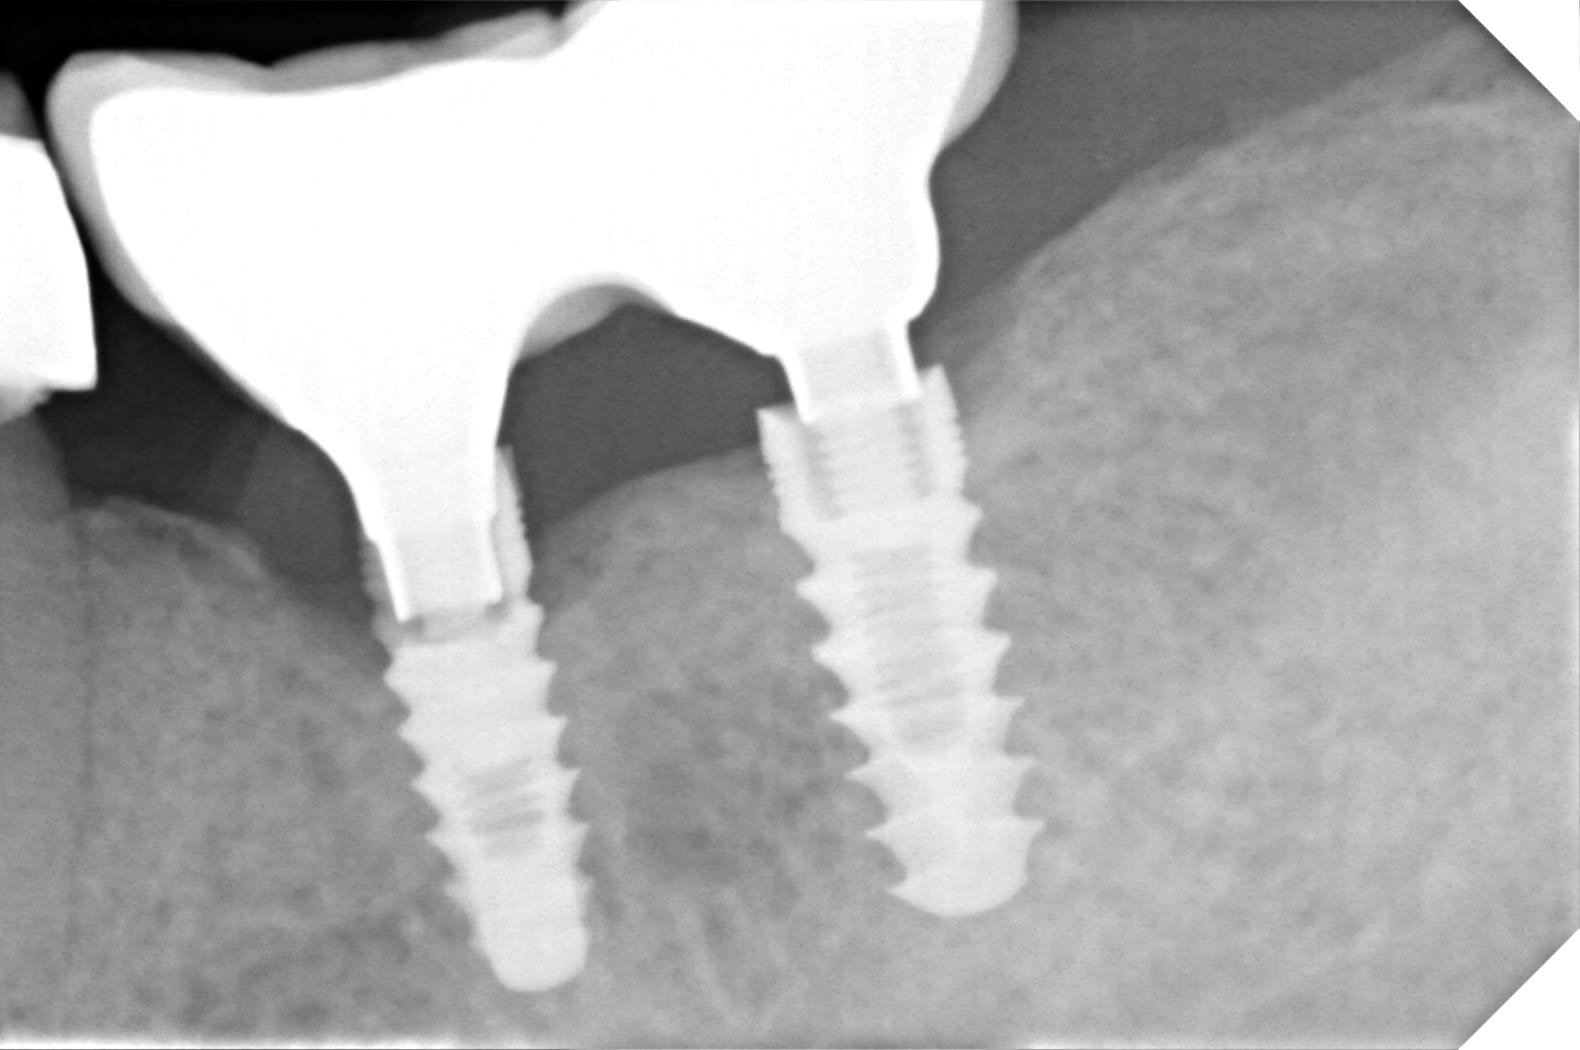

çà ressemble bien à çà:

https://www.spotimplant.com/fr/implants-dentaire/implant-microdent-system/e3kc

fiabilité de l'identification je dirais 90%

c'est moi ou le premier est pété au col? (ce qui expliquerait la cratérisation)

En effet on dirait qu'un fragment du col de l'implant manque, à déposer après vérification!

En effet j'ai récupéré un cas bien pourri avec inadaptation totale des ccmi et fracture du col implantaire.